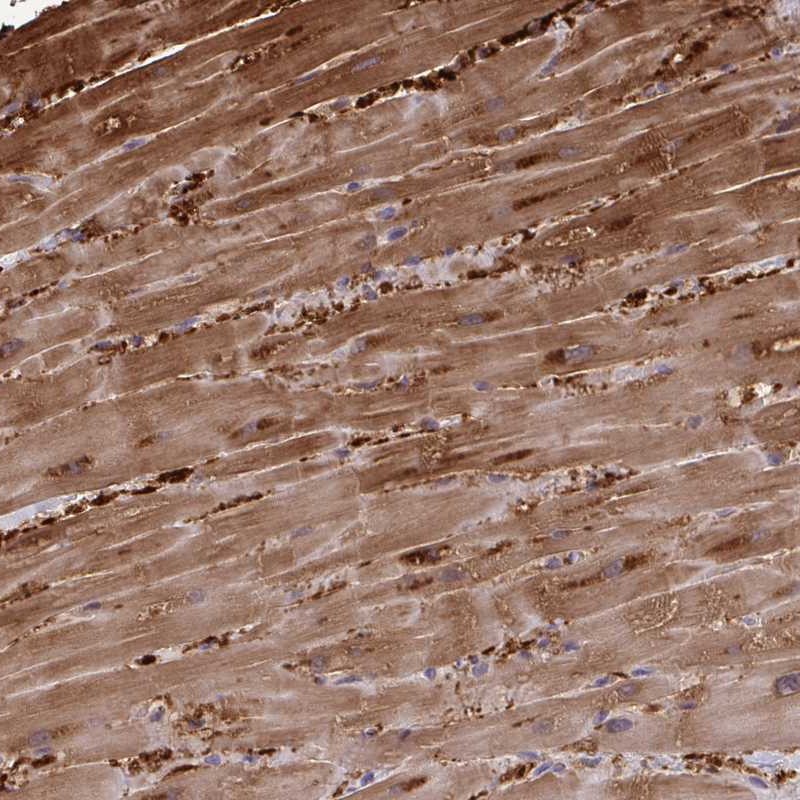

Immunohistochemistry analysis in human heart muscle and duodenum tissues using Anti-FABP3 antibody. Corresponding FABP3 RNA-seq data are presented for the same tissues.